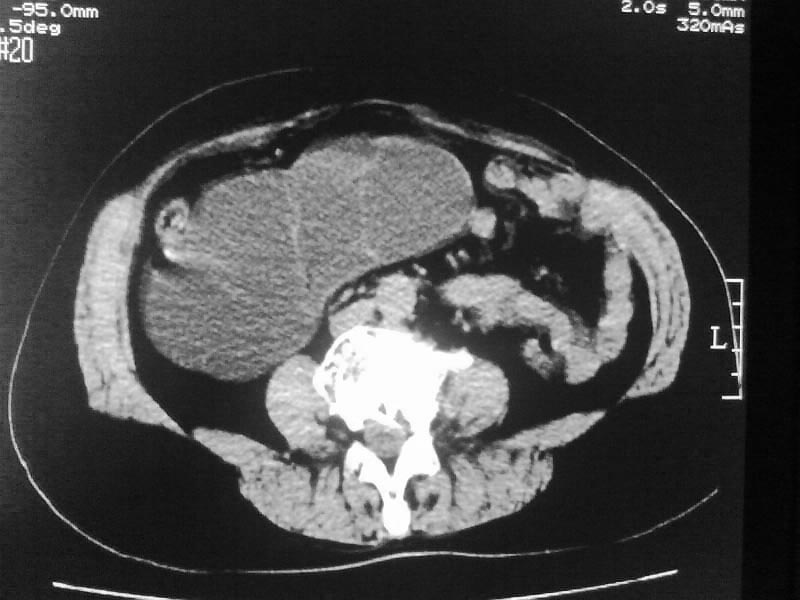

标题: CT20044:女,45岁,腰痛2年,双肾结石,右输尿管结石,右肾重度积 [打印本页]

标题: CT20044:女,45岁,腰痛2年,双肾结石,右输尿管结石,右肾重度积

加扫下输尿管和膀胱吧,先排除下面的大结石所致的积水;

再排除下面的压迫性病灶;

不像普通的积水,密度像是积脓;

双肾结石、双输尿管结石并右肾积水。